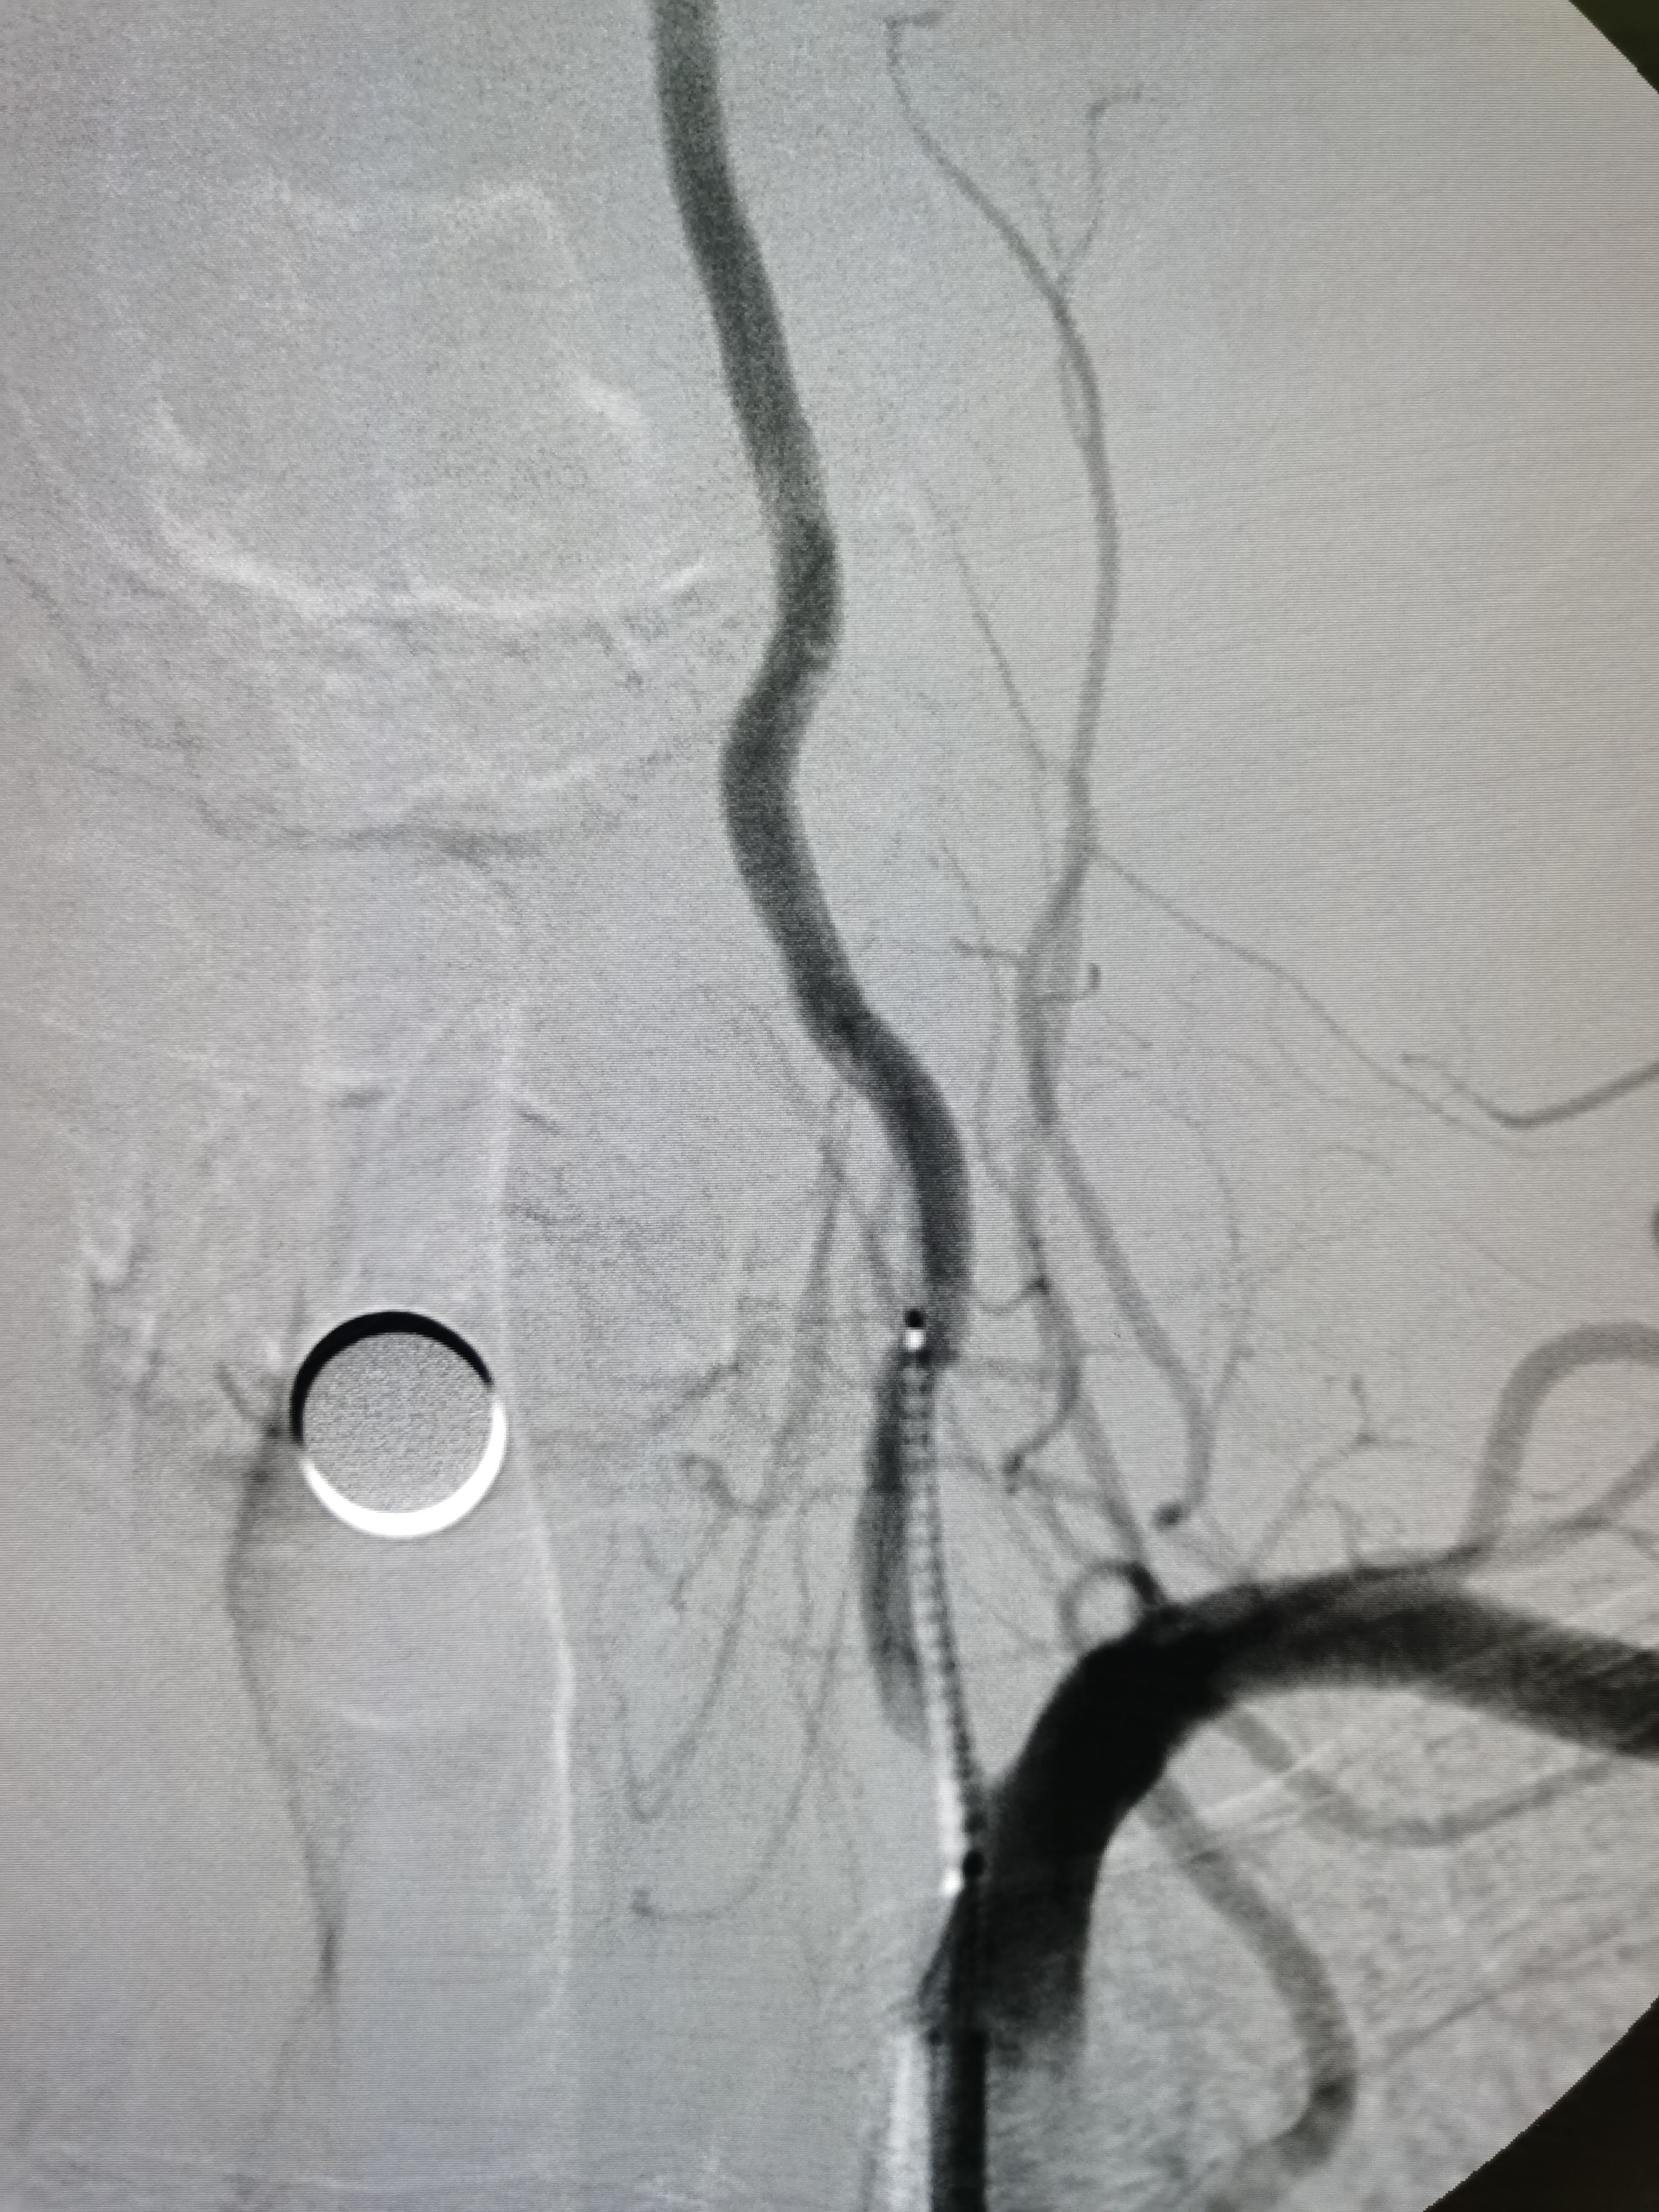

将8F导引导管送至左侧锁骨下动脉近左椎动脉起始部,微导丝顺利通过病变,2.0/20球囊预扩病变。

3、手术过程中,先用小球囊扩张病变,观察血栓情况,及时应用支架全程覆盖血栓及病变部位,成形满意。